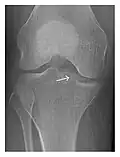

Occult osseous injuries may result from a direct blow to the bone by compressive forces of adjacent bones against one another or by traction forces during an avulsion injury. Lesions in the tibial plateau, hip, ankle, and wrist are often missed. In a tibial plateau fracture, any disruption of the posterior and anterior cortical rims of the plateau should be sought. Impaction of subchondral bone will appear as an increased sclerosis of the subchondral bone (Figure 1). In the hip, posterior acetabular fractures also present subtle radiographic findings. The acetabular lines should then be carefully examined keeping in mind that the posterior rim, which is harder to see on X-rays, is more frequently fractured than the anterior rim (Figure 2). In the wrist, detection of carpal bone fractures is often challenging, with up to 18% of scaphoid fractures radiographically occult. Carpal fractures, especially the scaphoid, are associated with the risk of avascular necrosis. In apparently normal wrist radiographs from symptomatic patients, if there is history of a fall on an outstretched hand with pain in the anatomic snuffbox, suggesting scaphoid injury, the initial examination with posteroanterior, lateral, and pronation oblique views must be complemented by other specific views such as supination oblique and the "scaphoid" view A careful examination of cortices for evidence of discontinuity or offset and cancellous bone for lucency is necessary (Figure 3).[1]

Figure 3: A 26-year-old man presenting with wrist pain after being assaulted. (a) Initial anteroposterior radiograph shows a subtle linear lucency within the scaphoid extending to the scaphocapitate articular surface that was overlooked (arrow). (b) Initial "scaphoid" view was negative. (c) Followup anteroposterior radiographs, 12 days later, shows obvious scaphoid fracture (arrows).[1]